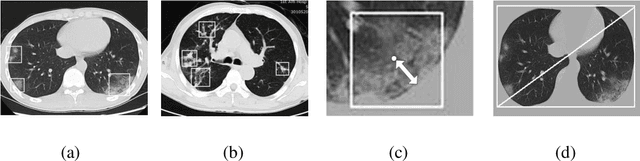

Abstract:We found that the real time reverse transcription-polymerase chain reaction (RT-PCR) detection of viral RNA from sputum or nasopharyngeal swab has a relatively low positive rate in the early stage to determine COVID-19 (named by the World Health Organization). The manifestations of computed tomography (CT) imaging of COVID-19 had their own characteristics, which are different from other types of viral pneumonia, such as Influenza-A viral pneumonia. Therefore, clinical doctors call for another early diagnostic criteria for this new type of pneumonia as soon as possible.This study aimed to establish an early screening model to distinguish COVID-19 pneumonia from Influenza-A viral pneumonia and healthy cases with pulmonary CT images using deep learning techniques. The candidate infection regions were first segmented out using a 3-dimensional deep learning model from pulmonary CT image set. These separated images were then categorized into COVID-19, Influenza-A viral pneumonia and irrelevant to infection groups, together with the corresponding confidence scores using a location-attention classification model. Finally the infection type and total confidence score of this CT case were calculated with Noisy-or Bayesian function.The experiments result of benchmark dataset showed that the overall accuracy was 86.7 % from the perspective of CT cases as a whole.The deep learning models established in this study were effective for the early screening of COVID-19 patients and demonstrated to be a promising supplementary diagnostic method for frontline clinical doctors.